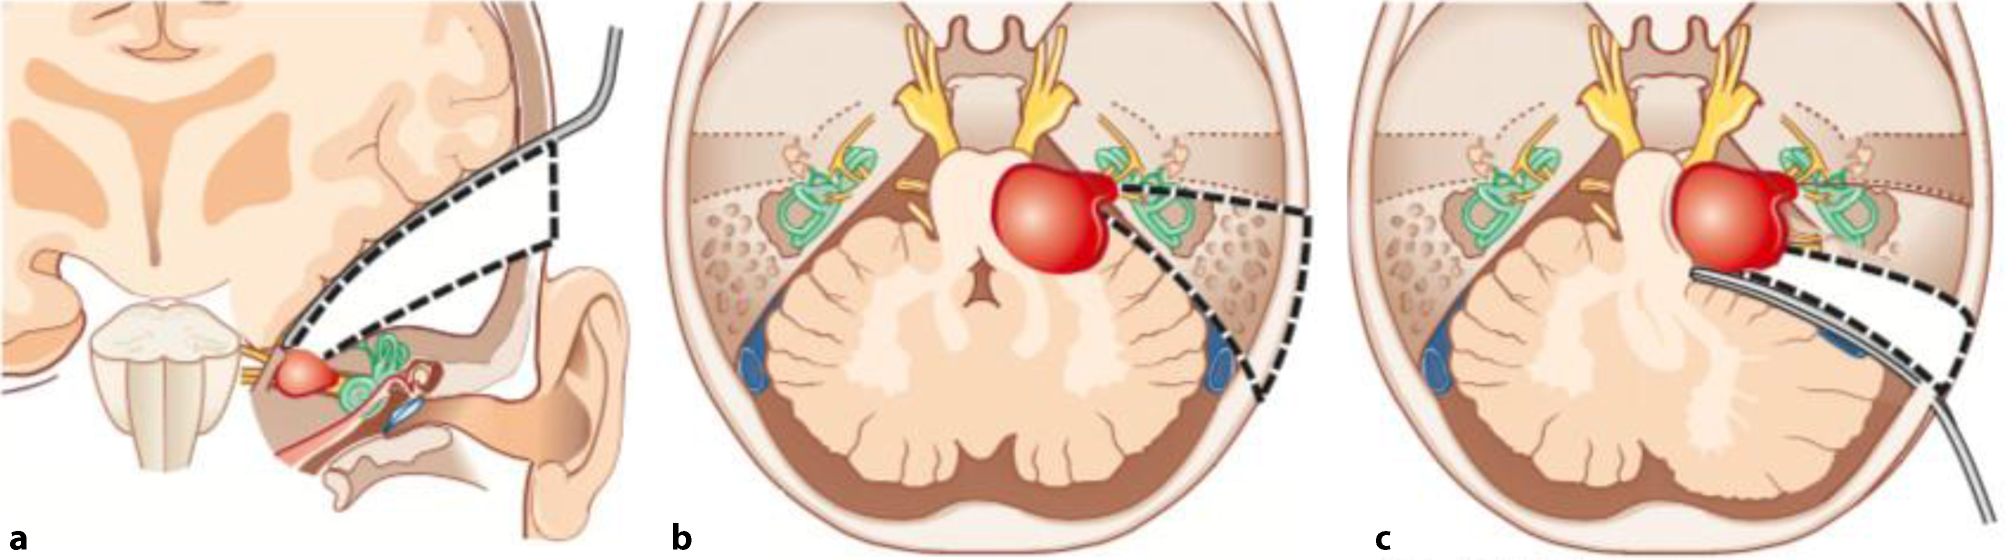

Studien zeigten, dass bei einer annähernd kompletten Resektion („near total resection“, <2 % Residualtumor) selten ein neuerliches Wachstum (0,0–3,5 %, [13]) zu erwarten ist. Jedoch ist bei einer subtotalen Resektion, welche als Entfernung von <95 bis <98 % der Tumormasse definiert wird, in 18,4 bis 73,9 % mit einem neuerlichen Tumorwachstum zu rechnen [14]. Chirurgisch kommen drei verschiedene Zugangswege in Frage (Abb. 2; [15]). Welcher Zugangsweg für einen bestimmten Patienten sinnvoll ist, hängt von der Lage und Ausdehnung des Tumors, dem Hörvermögen und dem Wunsch des Patienten ab.

Abb. 2

Veranschaulichung aller drei Zugänge zum Kleinhirnbrückenwinkel. a Middle Fossa-Zugang: Temporallappen wird retrahiert, um zum Tumor zu gelangen. Erhalt des Gehörs möglich. b Translabyrinthärer Zugang: Keine Retraktion des Gehirns notwendig. Untere Hirnnerven sind nicht exponiert. Kein Erhalt des Gehörs möglich. c Retrosigmoidaler Zugang: Retraktion des Kleinhirns. Untere Hinrnerven sind exponiert. Erhalt des Gehörs möglich. Illustration aus „Otology, Neurotology, and Lateral Skull Base Surgery: An Illustrated Handbook“ von Adunka und Buchman mit freundlicher Erlaubnis des Georg Thieme Verlags [15]

Retrosigmoidale (retromastoidale) Zugänge sind vor allem für Tumore mit großem extrameatalen Anteil geeignet [1]. Hierbei präpariert der Chirurg den Tumor unter einer weitreichenden Exposition der hinteren Schädelgrube. Allerdings sind VS, die weit in den lateralen Anteil des inneren Gehörgangs (Fundus) reichen, oft nicht ausreichend erreichbar und somit nicht komplett hörerhaltend resezierbar.

Subtemporale Zugänge („Middle Fossa“) sind vor allem für Patienten mit intrameatalen und fundusnahen VS, welche nur eine geringe Ausbreitung außerhalb des inneren Gehörgangs besitzen, sinnvoll [1].

Translabyrinthäre VS Resektionen implizieren einen Zugang durch den vestibulären Anteil des Innenohrs und werden daher primär bei Patienten ohne funktionellem Gehör eingesetzt. Die hierbei durchgeführte Mastoidektomie und Labyrinthektomie ermöglicht die schonende Entfernung des VS, da auf das Kleinhirn (und den Temporallappen) kein Druck ausgeübt werden muss und der Tumor schonend exponiert wird. Die Möglichkeit der Durchführung einer simultanen Cochlea Implantation macht diesen Zugang besonders interessant.